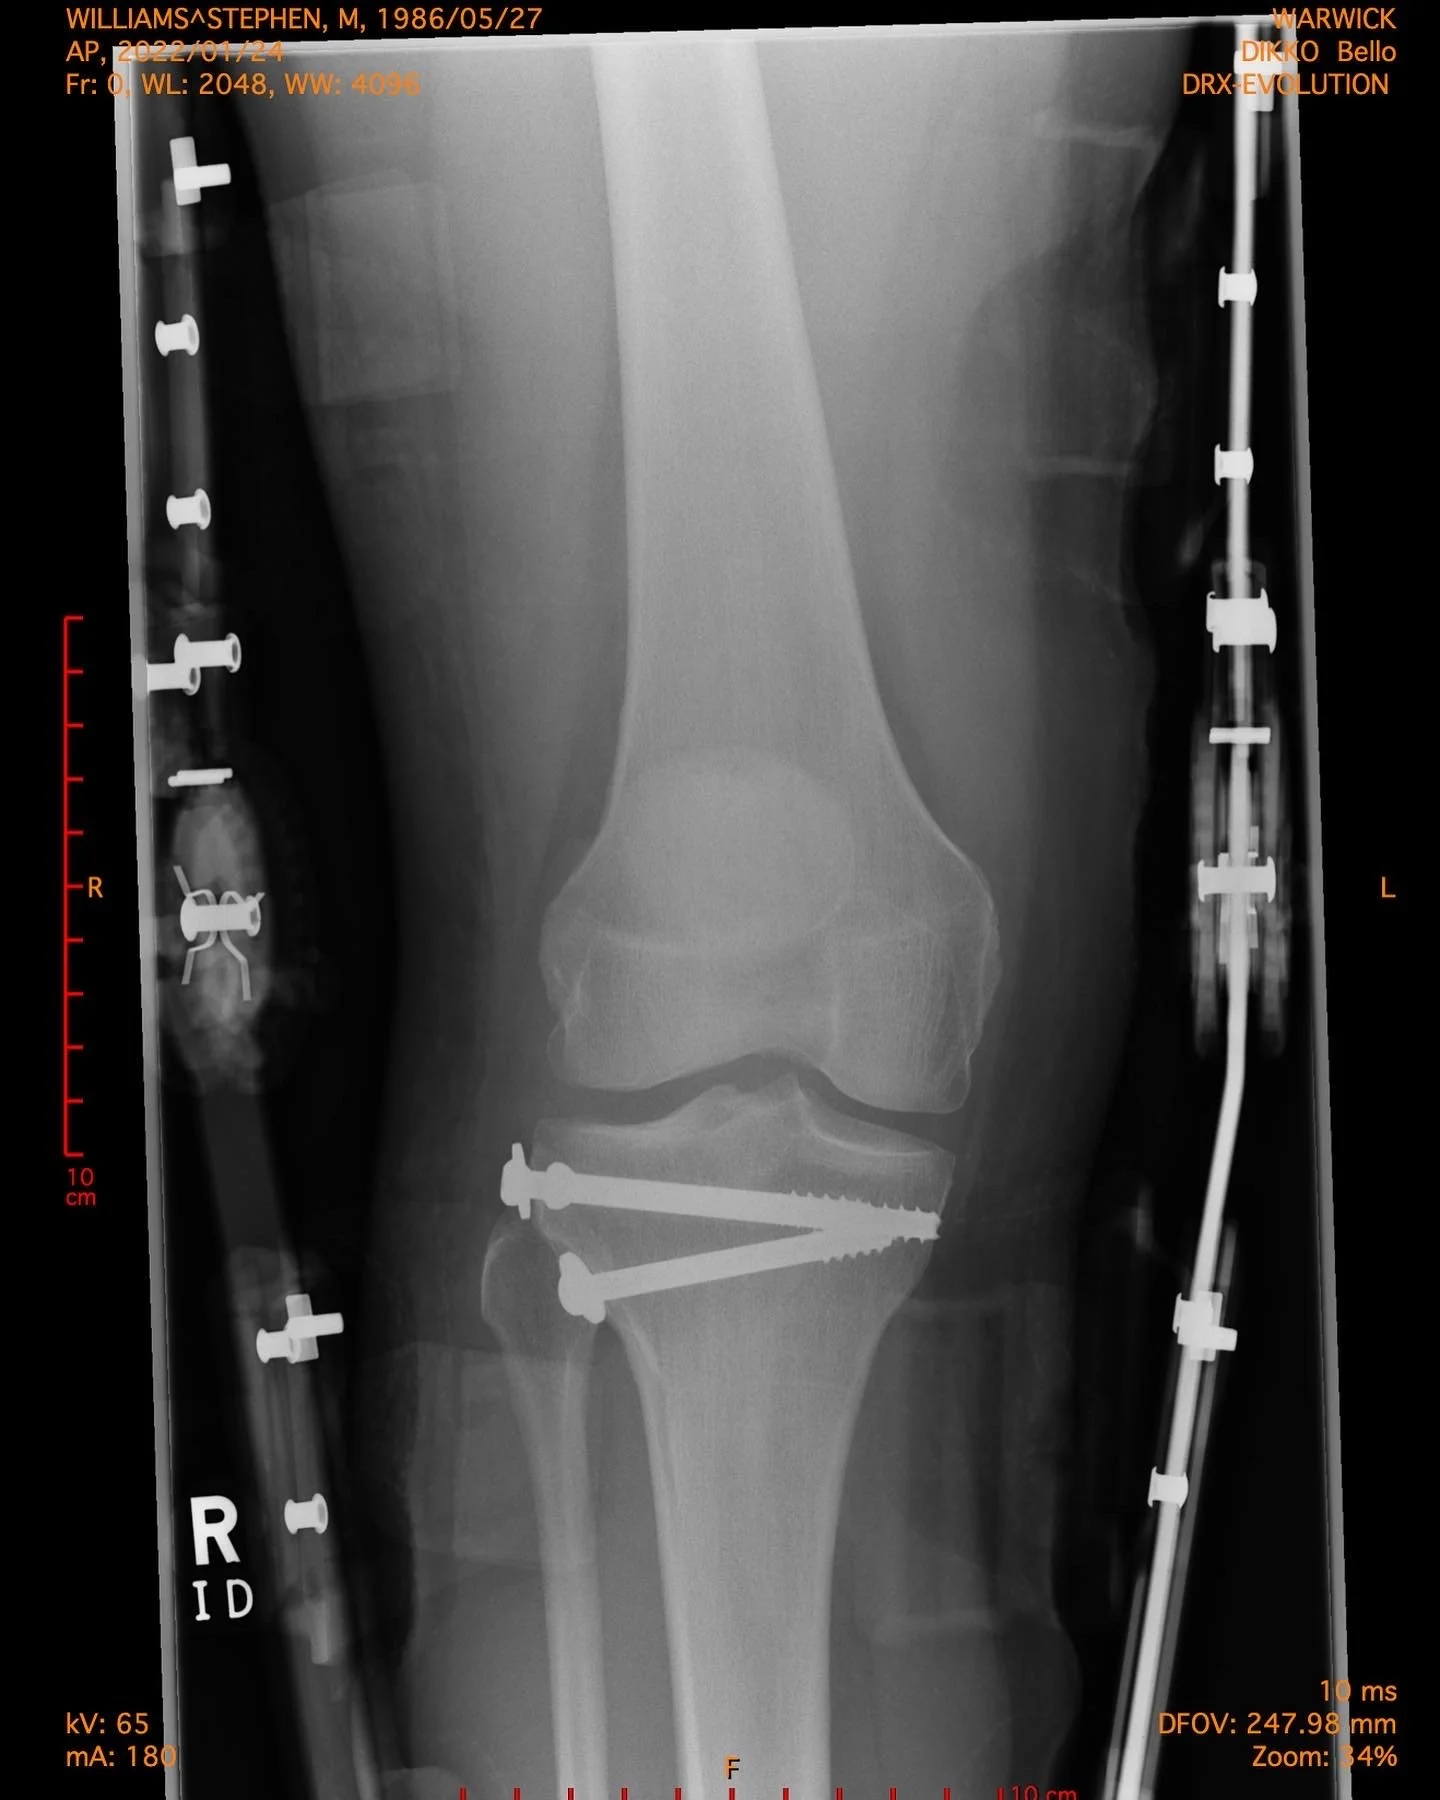

Tibial Plateau Fracture Repair Life After Tibial Plateau Fracture Surgery In this study, we aimed to evaluate the. Tibial plateau fractures (tpf) are uncommon and challenging for orthopedic surgeons with controversial reported outcomes. Most fractures take 4 months to completely heal. Initially, sports injury treatment using the p.r.i.c.e. A tibial plateau fracture is an injury where you break your bone and damage the cartilage on top of your tibia (bottom. Life After Tibial Plateau Fracture Surgery.

Tibial plateau fracture Schatzker II treated with ORIF followed by Life After Tibial Plateau Fracture Surgery Unlike other injuries where it is possible to avoid surgery, typically the best treatment is surgery after a tibial plateau. It’s important to strictly follow your doctor’s instructions to ensure that the bone heals. Tibial plateau fractures (tpf) are uncommon and challenging for orthopedic surgeons with controversial reported outcomes. In more severe cases, it can take up to 6 months.. Life After Tibial Plateau Fracture Surgery.

*UPDATED* A personal one My recovery from a tibial plateau fracture Life After Tibial Plateau Fracture Surgery Unlike other injuries where it is possible to avoid surgery, typically the best treatment is surgery after a tibial plateau. It’s important to strictly follow your doctor’s instructions to ensure that the bone heals. This can happen after a fall or a car. A tibial plateau fracture is an injury where you break your bone and damage the cartilage on. Life After Tibial Plateau Fracture Surgery.